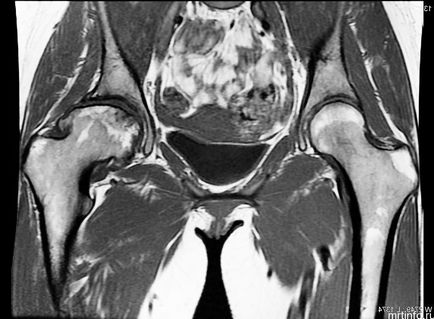

RMN-ul de sold, care arată cum să facă lecturi

RMN-ul a imaginii de sold

RMN-ul a articulației șoldului (comparație). A. normală articulația șoldului. B. articulatiei soldului afectat de artroza. B. artroplastia totală de șold.